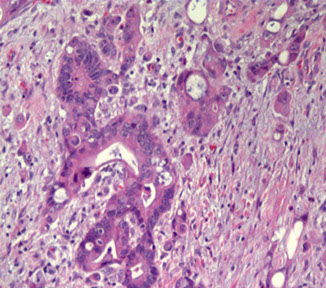

Nested urothelial carcinoma

- variant of urothelial ca originally recognized by its ability to mimic b9 conditions like proliferating von Brunn nests, esp in small bx's

- however, has a propensity to invade deep into bladder wall despite its low-grade morphology

- may be assoc c carcinoma in situ or conventional urothelial ca

- IHC: similar to typical UC (+ CK7 and p63, often CK20+)

Nested urothelial carcinoma [2]